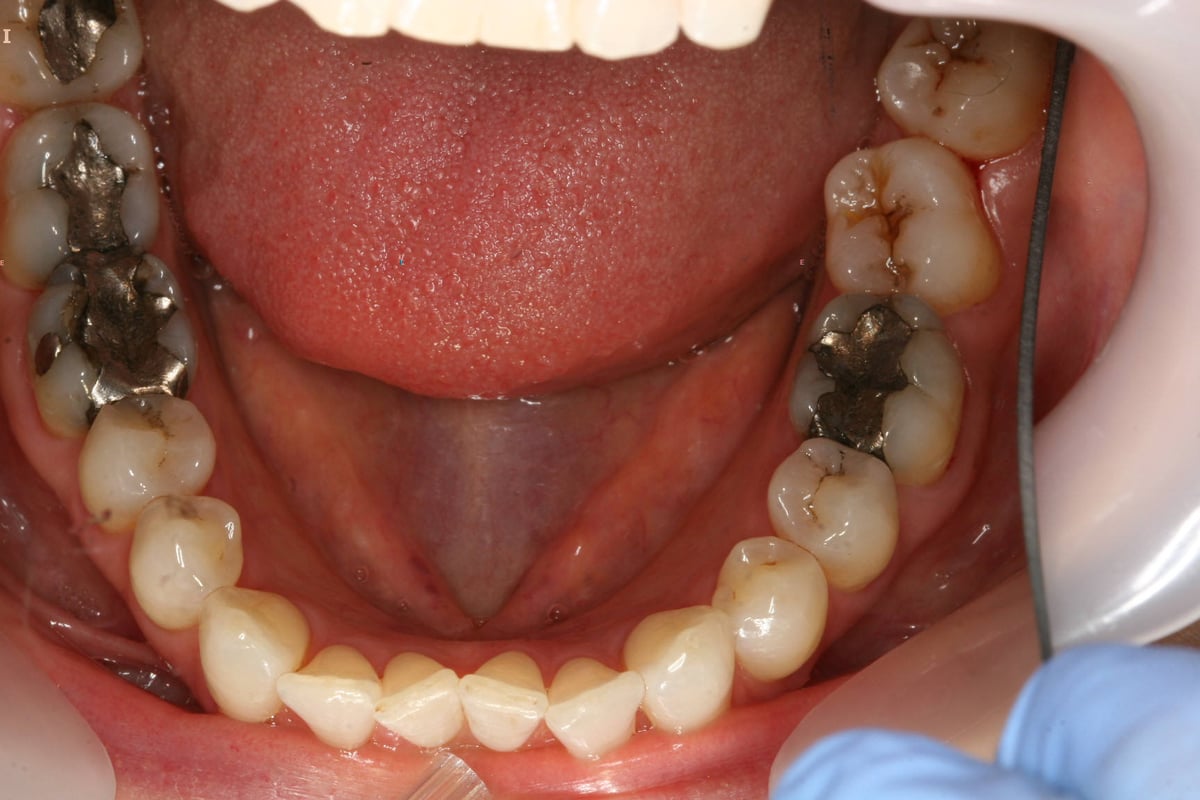

The beforeandafter of replacing silver fillings (amalgam) with white

Replacement of Amalgam Fillings Leederville Dental Perth's most What To Replace Amalgam Fillings With Amalgam, or silver, fillings are made with mercury, silver, tin and copper. Is it safe to have amalgam (silver) fillings? There are many alternatives to dental amalgam fillings, but biocompatibility should be considered when selecting a material. Should you have them removed? It is a relatively common procedure to replace amalgam fillings with composite fillings whether it's because of health. What To Replace Amalgam Fillings With.

Before & After Amalgam Fillings Replacement Dentist in Merced, CA What To Replace Amalgam Fillings With Composite fillings, ceramic fillings, gold fillings, and glass ionomer fillings are among the alternatives you can explore. It is a relatively common procedure to replace amalgam fillings with composite fillings whether it's because of health concerns or cosmetic preferences. Each has its advantages and disadvantages, so it’s. Amalgam, or silver, fillings are made with mercury, silver, tin and copper. Is. What To Replace Amalgam Fillings With.